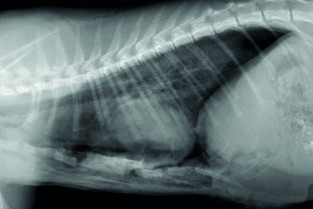

Le GEIM vous propose une séance de travaux pratiques de radiographies sur le thorax. Tous les aspects sont abordés sous la forme de TP de lecture de radiographies numériques sur station de travail Osirix sur Mac (3 vétérinaires maximum/ordinateur).

- décrire les principes à respecter pour obtenir une radiographie thoraciques de bonne qualité ;

- adopter une méthodologie pour interpréter les affections de la cage thoracique, de la plèvre, et du médiastin chez les carnivores domestiques ;

- décrire l’aspect normal et anormal de la cage thoracique, de la plèvre, et du médiastin chez les carnivores domestiques.